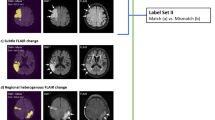

The activation map generated using the Grad-CAM technique applied on the validation DW images and classification score is shown in the figure, regions where the color is more towards red, represent areas activated by the CNN. The dark purple background represents areas that were not activated. Figure 2 shows the examples of correct classification, the first case was a normal image, the second one was classified as ACI with left frontal region being activated and the third one was classified as PCI where right cerebellar was activated by the CNN model. Figure 3 shows two misclassified sample images. First case was an ACI case with infarction area at right temporal lobe, but CNN misclassified it into normal. The second case was a PCI case with an area of DWI bright up over right cerebellum but CNN misclassified it into normal.

Example images of misclassification, the first case was right temporal lobe infarction, but miss-classified into normal by EfficientNet-b0 model (A), and second case was right cerebellar infarction but miss-classified into normal by the modified LeNet model (B). The number in bracket represent classification score.

Using Grad-CAM, we discovered that one potential explanation for the reasons for misclassification may be due to susceptibility artifact, which is a common finding at the air-bone interface of the temporal bone in DWI27,28. This artifact frequently creates patchy bright signal along bilateral petrous apex with spatial distortion on DWI which may have misled our training model so that it took the right temporal bright up region as an artifact in the first case of Fig. 3 and resulted in the misclassification. This susceptibility artifact occurs frequently in the clinical setting and can sometimes be difficult even for human readers to differentiate whether the DWI bright-up region is due to an artifact or representing true ischemic infarction.